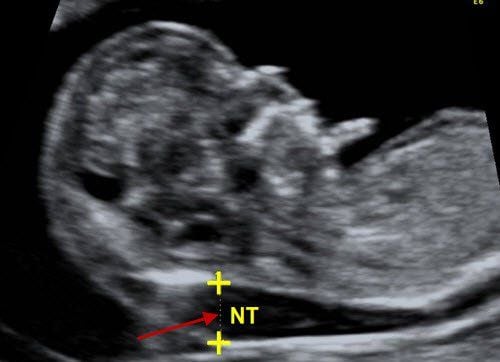

On September 20, I had an ultrasound and was confirmed to be pregnant, with the size of the gestational sac being 8mm. On the second ultrasound, which was on October 3, the result showed the gestational sac size to be 18mm, and the pregnancy was 5 weeks and 4 days. The edges of the amniotic sac were uniformly stretched, but no embryo or yolk sac could be seen. The trophoblast is thickened with no signs of bleeding or fluid accumulation around the sac, and there is nothing abnormal around the uterus. Could you please tell me if the absence of the embryo and yolk sac at 5 weeks means anything? Thank you, Doctor.

Based on the information you provided, two weeks after the gestational sac measured 8mm in the uterus, no embryo or fetal heartbeat has been detected. This is a concerning sign for the pregnancy. To obtain an accurate diagnosis, you should visit a reputable obstetrics center for a check-up and further consultation.